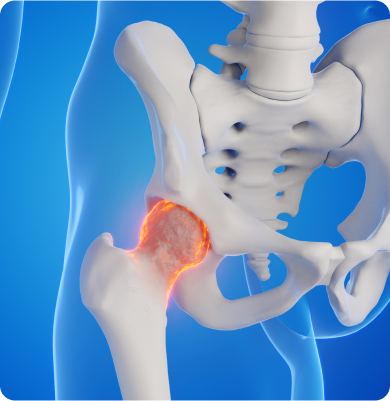

뼈에 혈액 공급이 부족해 뼈 조직이 죽고 그로 인해 뼈가 약해지고 변형되는 질환

외상, 과도한 알코올 섭취, 스테로이드 약물의 장기 사용, 혈액 순환 장애 등이 주요 원인입니다.